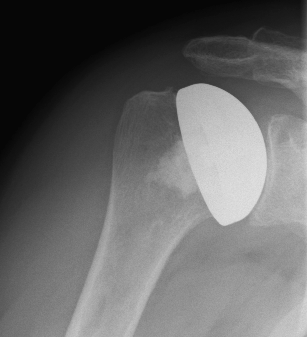

Surface replacement ("cap prosthesis" of the humeral head) in cases of mild omarthrosis and still well-preserved glenoid cavity

links: X-ray image of a cap prosthesis ("surface replacement")

right: cap prosthesis ("surface replacement", type "Durom" Fa. Zimmer)gkl